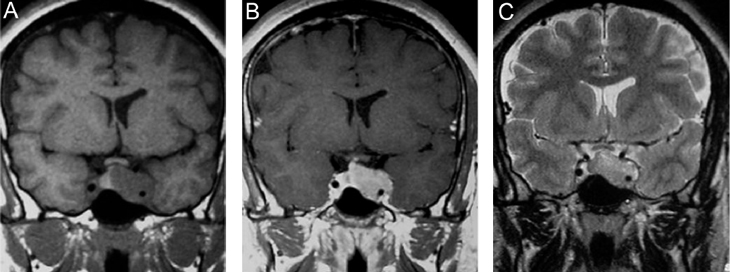

Anatomía normal de la glándula pituitaria

En los recién nacidos, la glándula tiene un borde superior convexo y presenta hiperseñal homogénea en secuencias T1w (Figura 3A). Durante el primer año de vida la adenohipófisis cambia su señal, pero se mantiene un foco de hiperseñal posterior donde se ubica la neurohipófisis (Figura 3B). A partir de los dos años de edad adquiere una altura < 6 mm, tamaño que se mantiene hasta la pubertad, período en que aumenta alcanzando en promedio 8 mm en niños y 10 mm en niñas, medidas que se mantienen en los adultos jóvenes17 (Figuras 4A, 4B y 4C). Durante el embarazo la hipófisis alcanza su mayor tamaño, con 12 mm de altura durante el último mes de gestación y en la primera semana posparto (Figura 5). La adenohipófisis aumenta en un 30% su tamaño, alcanzando su máximo volumen al tercer día posparto18, como resultado de la hipertrofia e hiperplasia de los lactotropos inducida por los estrógenos de la placenta. La neurohipófisis pierde su foco de hiperseñal durante el tercer trimestre, aunque las dimensiones del tallo hipofisiario y de la neurohipófisis no se modifican durante el embarazo.

En general, el volumen y la forma de la glándula pituitaria varían con la edad, el sexo y las condiciones fisiológicas del individuo; así, por ejemplo, la hiperplasia pituitaria asociada al hipotiroidismo primario puede simular un adenoma pituitario. Algunas variaciones en la morfología corresponden al hecho que la glándula pituitaria debe acomodarse a la forma y volumen de la silla turca, lo que hay que tener presente al evaluar sus características (Figuras 6A, 6B y 7).

Figura 3A. Corte sagital, secuencia T1w. Glándula pituitaria en un recién nacido, muestra hiperseñal homogénea normal a esta edad.

Figura 3B. Corte sagital, secuencia T1w. Glándula pituitaria en lactante de 2 meses, muestra disminución de la hiperseñal de la adenohipófisis.

Figura 4A. Corte sagital, secuencia T1w. Glándula pituitaria normal en adulto joven (27 años), muestra foco posterior de hiperseñal de la neurohipófisis (punta de flecha); la señal de la adenohipófisis es similar a la de la protuberancia.

Figura 4B. Corte sagital, secuencia T2w.en el mismo paciente, la glándula pituitaria, muestra la neurohipófisis con leve hiperseñal (punta de flecha); la señal de la adenohipófisis es también similar a la protuberancia en esta secuencia.

Figura 4C. Corte sagital, secuencia T1w post inyección de Gadolinio. La glándula pituitaria, muestra refuerzo normal incluyendo el tallo pituitario; en el cerebro solo se refuerzan las estructuras vasculares.